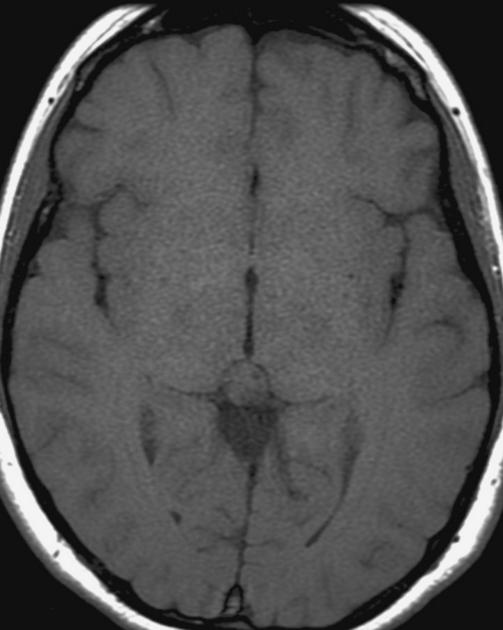

The general workup is MRI with T1/T2 images. Pineoblastomas are generally iso-enhancing on both T1 and T2, but T2 shows cystic components, at times becoming larger than the tumor itself. Surgical resection is treatment which also serves to provide tissue for diagnosis.

Pineocytoma T1 no contrast